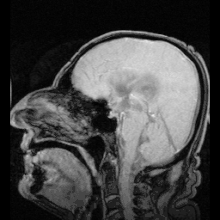

![]() The cerebrospinal fluid circulates in the subarachnoid space around the brain and spinal cord, and in the ventricles of the brain. | |

Cerebrospinal fluid (CSF) is a clear, colorless transcellular body fluid found within the meningeal tissue that surrounds the vertebrate brain and spinal cord, and in the ventricles of the brain.

CSF is mostly produced by specialized ependymal cells in the choroid plexuses of the ventricles of the brain, and absorbed in the arachnoid granulations. It is also produced by ependymal cells in the lining of the ventricles. In humans, there is about 125 mL of CSF at any one time, and about 500 mL is generated every day. CSF acts as a shock absorber, cushion or buffer, providing basic mechanical and immunological protection to the brain inside the skull. CSF also serves a vital function in the cerebral autoregulation of cerebral blood flow.

CSF occupies the subarachnoid space (between the arachnoid mater and the pia mater) and the ventricular system around and inside the brain and spinal cord. It fills the ventricles of the brain, cisterns, and sulci, as well as the central canal of the spinal cord. There is also a connection from the subarachnoid space to the bony labyrinth of the inner ear via the perilymphatic duct where the perilymph is continuous with the cerebrospinal fluid. The ependymal cells of the choroid plexus have multiple motile cilia on their apical surfaces that beat to move the CSF through the ventricles.

In humans, there is about 125–150 mL of CSF at any one time.[1] This CSF circulates within the ventricular system of the brain. The ventricles are a series of cavities filled with CSF. The majority of CSF is produced from within the two lateral ventricles. From here, CSF passes through the interventricular foramina to the third ventricle, then the cerebral aqueduct to the fourth ventricle. From the fourth ventricle, the fluid passes into the subarachnoid space through four openings – the central canal of the spinal cord, the median aperture, and the two lateral apertures.[1] CSF is present within the subarachnoid space, which covers the brain and spinal cord, and stretches below the end of the spinal cord to the sacrum.[1][2] There is a connection from the subarachnoid space to the bony labyrinth of the inner ear making the cerebrospinal fluid continuous with the perilymph in 93% of people.[3]